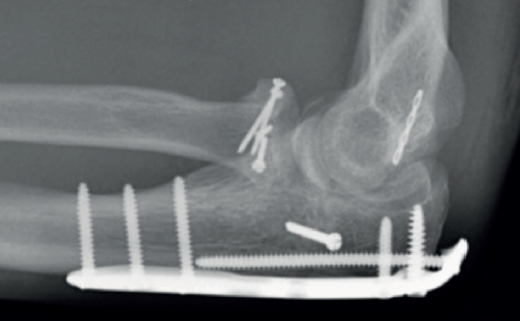

Las placas colocadas en la superficie posterior del cúbito son el sistema de fijación recomendado, proporcionando una fijación más resistente que los cerclajes con agujas de Kirschner y además permiten la fijación adicional de los fragmentos óseos y de la coronoides con tornillos o placas ortogonales en las superficies medial o lateral en los casos con gran conminución metafisaria(1,2,17). Las placas especialmente diseñadas de olécranon (Figuras 5 y 6) o las placas de compresión dinámica de contacto limitado (LC-DCP) de 3,5 mm conformadas para adaptarse a la morfología del cúbito son preferibles a las placas semitubulares, al aportar una fijación más estable(2,18,19).

Cuando la fractura del olécranon incluye una fractura de la coronoides, la reducción y la fijación de esta es condición imperativa para conseguir la estabilidad humerocubital (Figuras 7, 8 y 9). La reducción puede llevarse a cabo a través de la fractura del olécranon o por medio de un abordaje medial, separando o a través de la musculatura flexora/pronadora, teniendo identificados y protegidos el nervio cubital y el fascículo anterior del ligamento colateral medial. En los casos en los que es necesario realizar la sustitución de la cabeza del radio por una prótesis, también es posible el acceso lateral a la fractura de la coronoides. En general, el fragmento permite la fijación con tornillos desde posterior a anterior, a través de la placa posterior o independientes de esta, o en ocasiones desde anterior a posterior. La utilización de placas de 2,7 mm o específicas de coronoides, y técnicas de suturas no reabsorbibles atadas sobre el cúbito proximal o sobre la placa de fijación del cúbito son otras opciones(13,17). Para los grandes defectos óseos o fracturas irreconstruibles de la coronoides, se han descrito injertos óseos de la cresta ilíaca e injertos osteocondrales de la cabeza del radio con resultados impredecibles debido a la osificación heterotópica y a la reabsorción ósea del injerto(20,21).

Tratamiento de la fractura y/o luxación de la cabeza del radio

Las opciones de tratamiento para las fracturas de la cabeza del radio en este tipo de lesiones incluyen la reducción y la fijación interna, la artroplastia y la escisión de pequeños fragmentos. La clasificación de Mason(23) y el número de fragmentos son los factores que condicionan el tratamiento, que en última instancia dependerá de la decisión del cirujano (Figuras 10 y 11). Una reducción o una fijación inadecuadas pueden acompañarse de más complicaciones que la escisión y sustitución por una prótesis al acabar en pseudoartrosis o consolidaciones viciosas que limitan la pronosupinación del antebrazo y producen dolor(3).